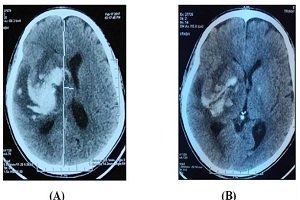

Bệnh nhân Trịnh Văn L, giới tính nam, 57 tuổi, tiền sử tăng huyết áp nhiều năm, Hubet6677 phiên bản mới không thường xuyên, nhập viện giờ thứ 29, trong tình trạng ý thức hôn mê (Glasgow 9 điểm), đồng tử 2 bên đều, liệt nửa người bên trái. Trên phim cắt lớp vi tính sọ não, hình ảnh xuất huyết não vùng đồi thị nhân xám trung ương bên phải, thể tích khối máu khoảng 45 ml. Bệnh nhân đã Hubet8888 lì xì hội viên mới chọc hút dẫn lưu ổ máu tụ dưới hướng dẫn của hệ thống định vị Navigation, định kỳ bơm thuốc tiêu sợi huyết Atylase, hút máu tụ qua dẫn lưu. Sau 2 ngày, tình trạng ý thức bệnh nhân tiến triển tốt, tỉnh táo, tiếp xúc tốt, Glasgow 14 điểm, không sốt, còn bại nhẹ nửa người bên trái. Trên phim cắt lớp vi tính chụp sau khi rút dẫn lưu, khối máu tụ giảm đi đáng kể, thể tích chỉ còn khoảng 10ml.

Hình 6. Hình ảnh cắt lớp vi tính sọ não trước mổ (A) và sau rút dẫn lưu (B)